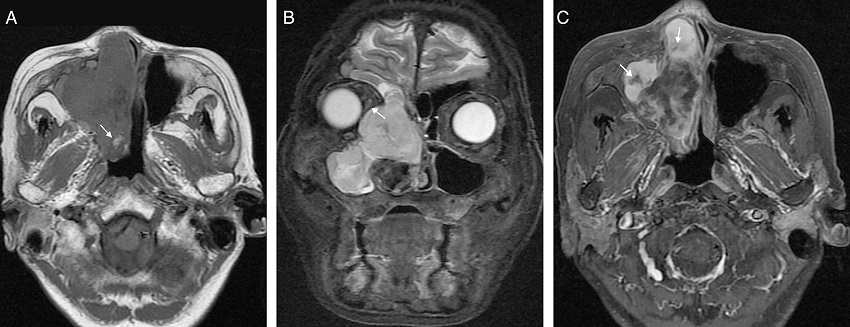

Diagnostic imaging included CT and MRI. The coronal and axial CT images showed a soft-tissue mass of right ethmoidal sinus, involving the right maxillary sinus, right frontal sinus and right nasal cavity. Bone erosion was observed in the right lamina of ethmoidal cells. The soft-tissue mass invaded the bony wall of right orbit and compressed the right eyeball (Fig. 1). MRI demonstrated the same appearances (Fig. 2). In additional, the mucous membrane of left ethmoidal sinus and bilateral sphenoid sinus were also compromised. Contrast-enhanced MRI confirmed heterogeneous enhancement of the lesion. Striped low-signal intensity was seen in the lesion.

Most of the tumors showed nonspecific various signal intensity on CT and MR images.1,7 CT can help evaluate bone destruction and sinonasal soft masses. MRI is the best tool to delineate soft tissue extension and compression of surrounding tissues.

The most common CT features are aggressive bone destruction and compressive bony absorption of sinus wall. The lesion easily erodes ipsilateral orbital medial wall in ethmoidal cells. In our case, ipsilateral orbital medial was destroyed and medial rectus and optic nerve were compressed to right side. On CT, the soft tissue mass shows isodensity or low density. Calcification foci can be found in some lesions.1 Striped calcification was found in our case. The tumor shows inhomogeneous iso-hyperintensity on T1WI, and mixed signal on T2WI. The collagenous fiber is hypointense while the liquefaction necrosis and mucoid degeneration are hyperintense on T2WI. Contrast-enhanced MRI confirmed homogeneous enhancement of the solid portion of lesion. The liquefaction necrosis and cystic degeneration are more significant in UHPS than other soft tissue tumors. The bigger the mass is, more common liquefaction necrosis and cystic degeneration are.8

Based on our case and literatures,1-3,5,6 we found the following imaging features of UHPS in the paranasal sinuses and nasal cavity: (i) the lesion fills up the whole paranasal sinus, (ii) aggressive bone destruction of sinus wall, (iii) erodes ipsilateral orbital medial wall, (iv) collagenous fiber, (v) homogeneous enhancement of the solid portion of lesion, (vi) liquefaction necrosis and cystic degeneration, and (vii) calcification.

UHPS of paranasal sinus and orbit is very rare. CT and MRI were useful for tumor delineation. Imaging findings suggested malignancy, but are nonspecific to UHPS. On MRI, the tumor shows inhomogeneous signal intensity, which may reflect the complex histologic components of the tumor.